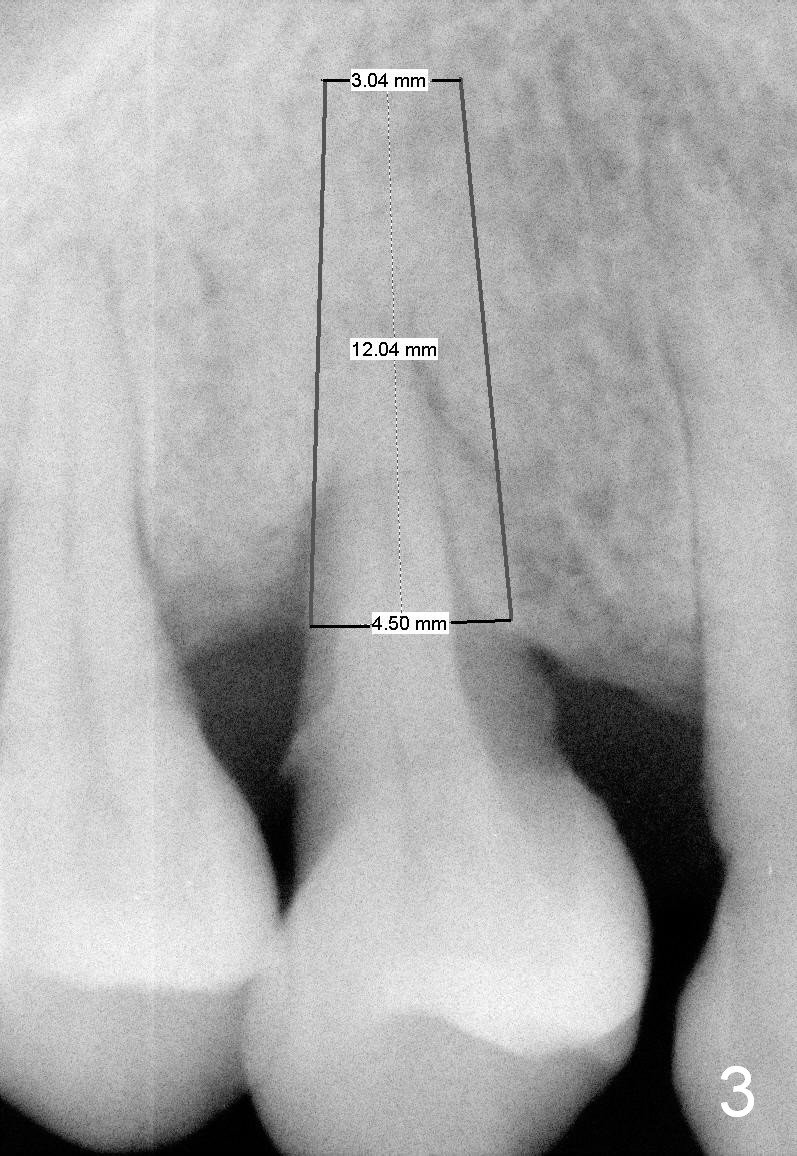

A 43-year-old lady has generalized moderate localized advanced chronic periodontits (Fig.1,2). In spite of 4 quadrant scaling & root planing, the tooth #19 develops 2 perio abscesses (Fig.4 with insertion of 2 guttae perchae); periodontal ligament spaces increases (compare Fig.2,4). It appears that the tooth is non salvageable and should be replaced with an immediate implant (Fig.5). The extraction socket will be treated with Metronidazole. A 2 mm pilot drill is used to start osteotomy in the septum (14 mm deep), followed by reamers until 3.5 mm. A 5x17 mm tap is placed to test stability. If the stability is high, place a 5.3x12 mm SM implant. If insertion torque is too high, use the corresponding drill before re-place the implant. Collagen dressing is placed in the peripheral and deep portion of the sockets, while bone graft in the top portion of the sockets (near implant threads). Use 1 or 2 amalgam carriers to deliver the graft lateral to the implant precisely so that a cover screw does not have to be placed. Next place a cemented abutment. If trajectory of the implant is correct, an abutment as large as 7.8x5(3) mm could be used (pink). Fabricate an immediate provisional. Do not over trim the margin of the provisional so that it can cover the socket completely.